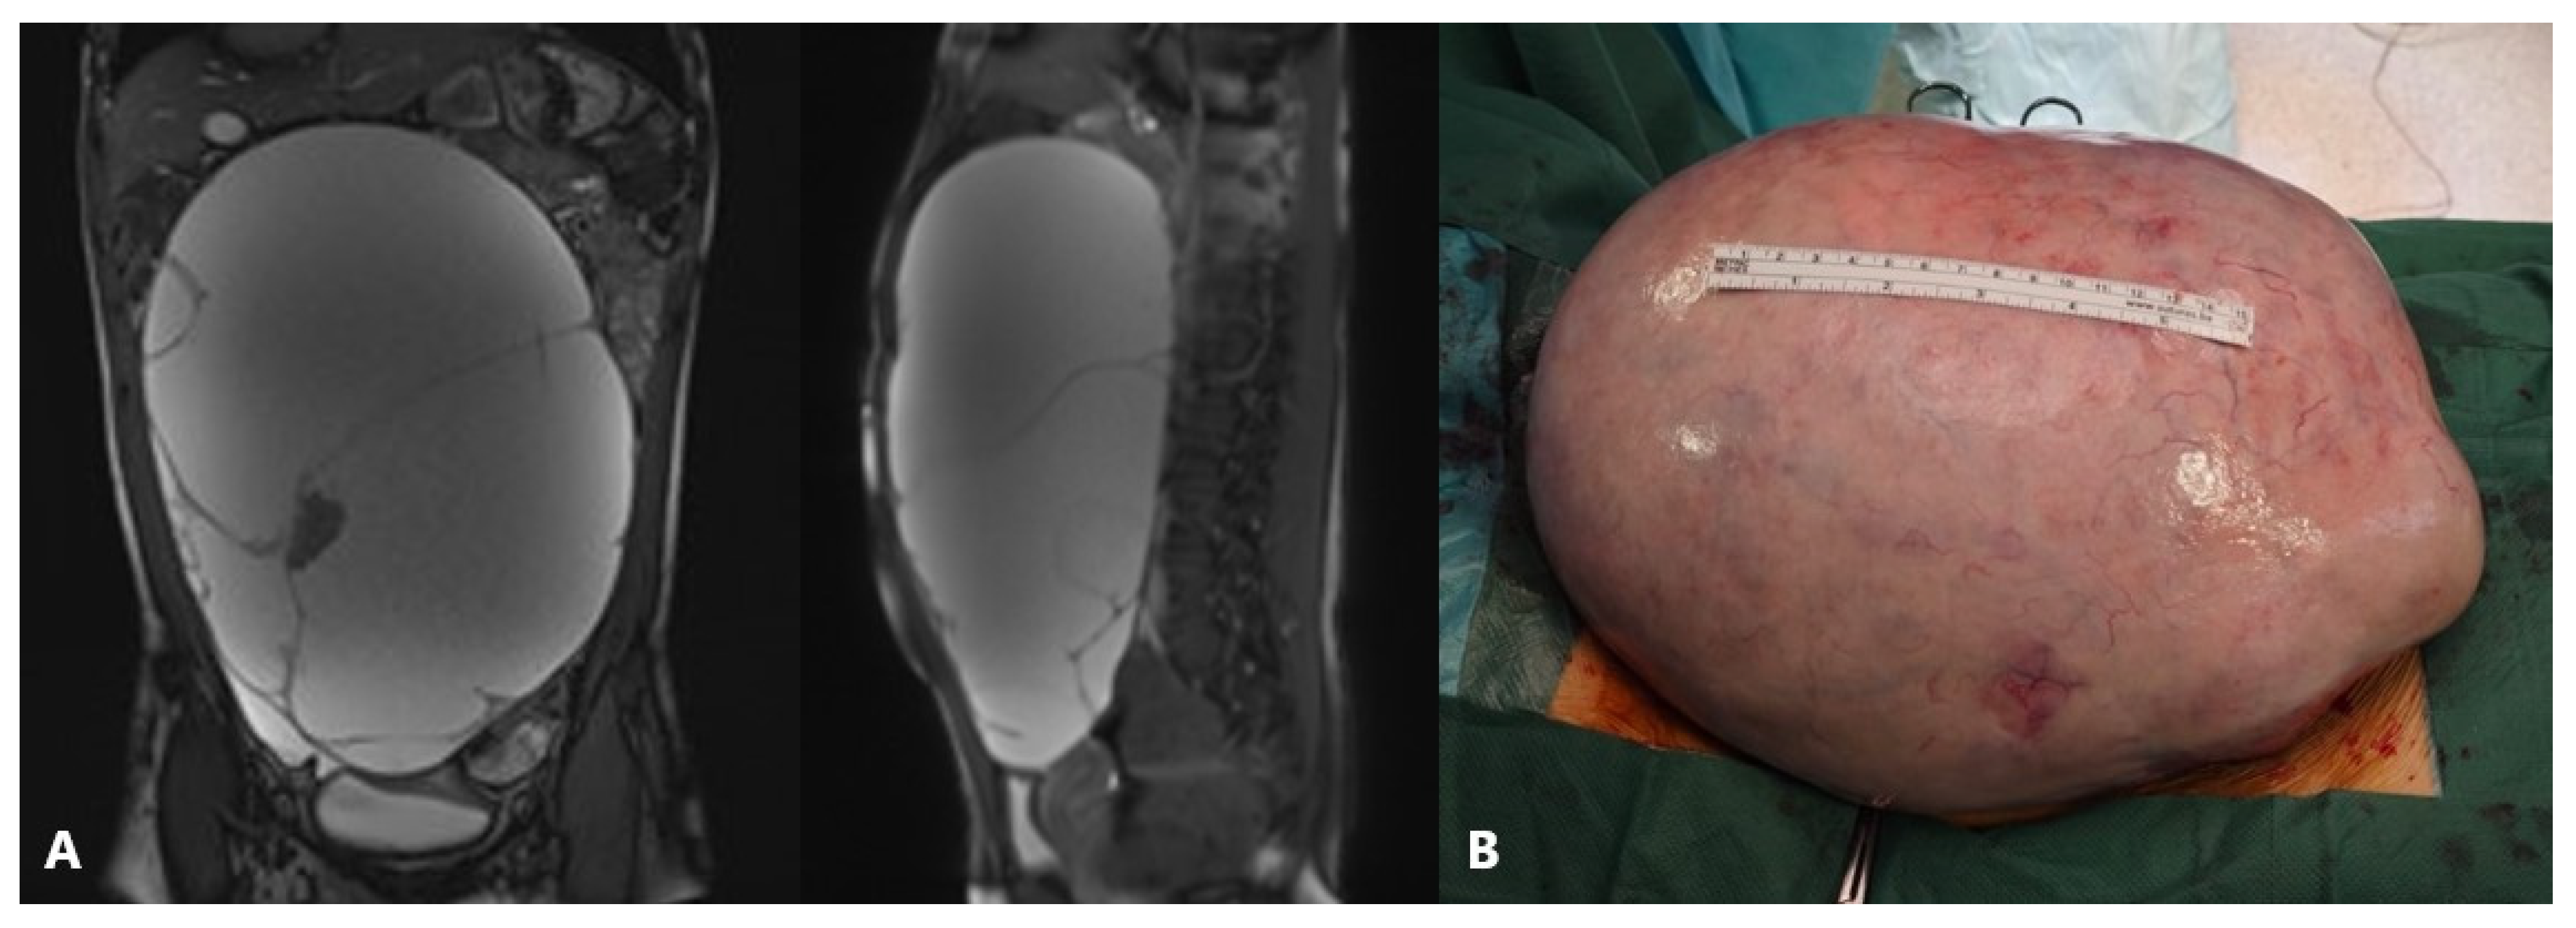

Figure 4.

An 11-year-old girl noticed that her stomach was growing along with pain, nausea, and a palpable mass. Ultrasound and MRI revealed bilateral ovarian tumor inhomogeneous solid cystic masses similar to dermoid, left 13 cm, right 5 cm in diameter. Tumor markers were not increased, and due to the size of the tumor, a laparotomy approach was decided. Intraoperative findings: bilateral asymmetrical ovarian masses and bilateral cystectomy were performed. A pathohistological examination revealed a mature teratoma. Source: Archive of the Department of Obstetrics and Gynecology, Clinical Hospital Merkur.